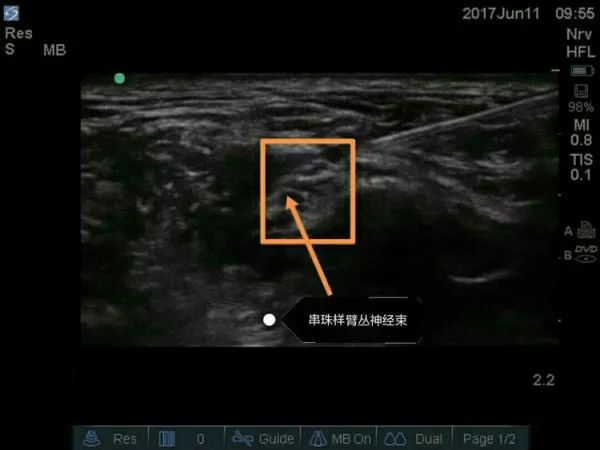

超声下肌间沟水平臂丛的走行图像,上面是胸锁乳突肌,左右是前、中斜角肌。肌间沟水平下可清楚看到呈串珠样的臂丛,C5、C6、C7等。请大家注意下,有的时候能看见5个“串珠”,不要以为是臂丛的5个根即C5、C6、C7、C8、T1,肌间沟往往是在颈椎7水平,怎么可能看到C8、T1,其实就是C5、C6、C7,那为什么是5个“串珠”?因为C6及C7在肌间沟水平已经分出2根,要避免在这2根汇合处之间穿刺而造成C6及C7的神经损伤。